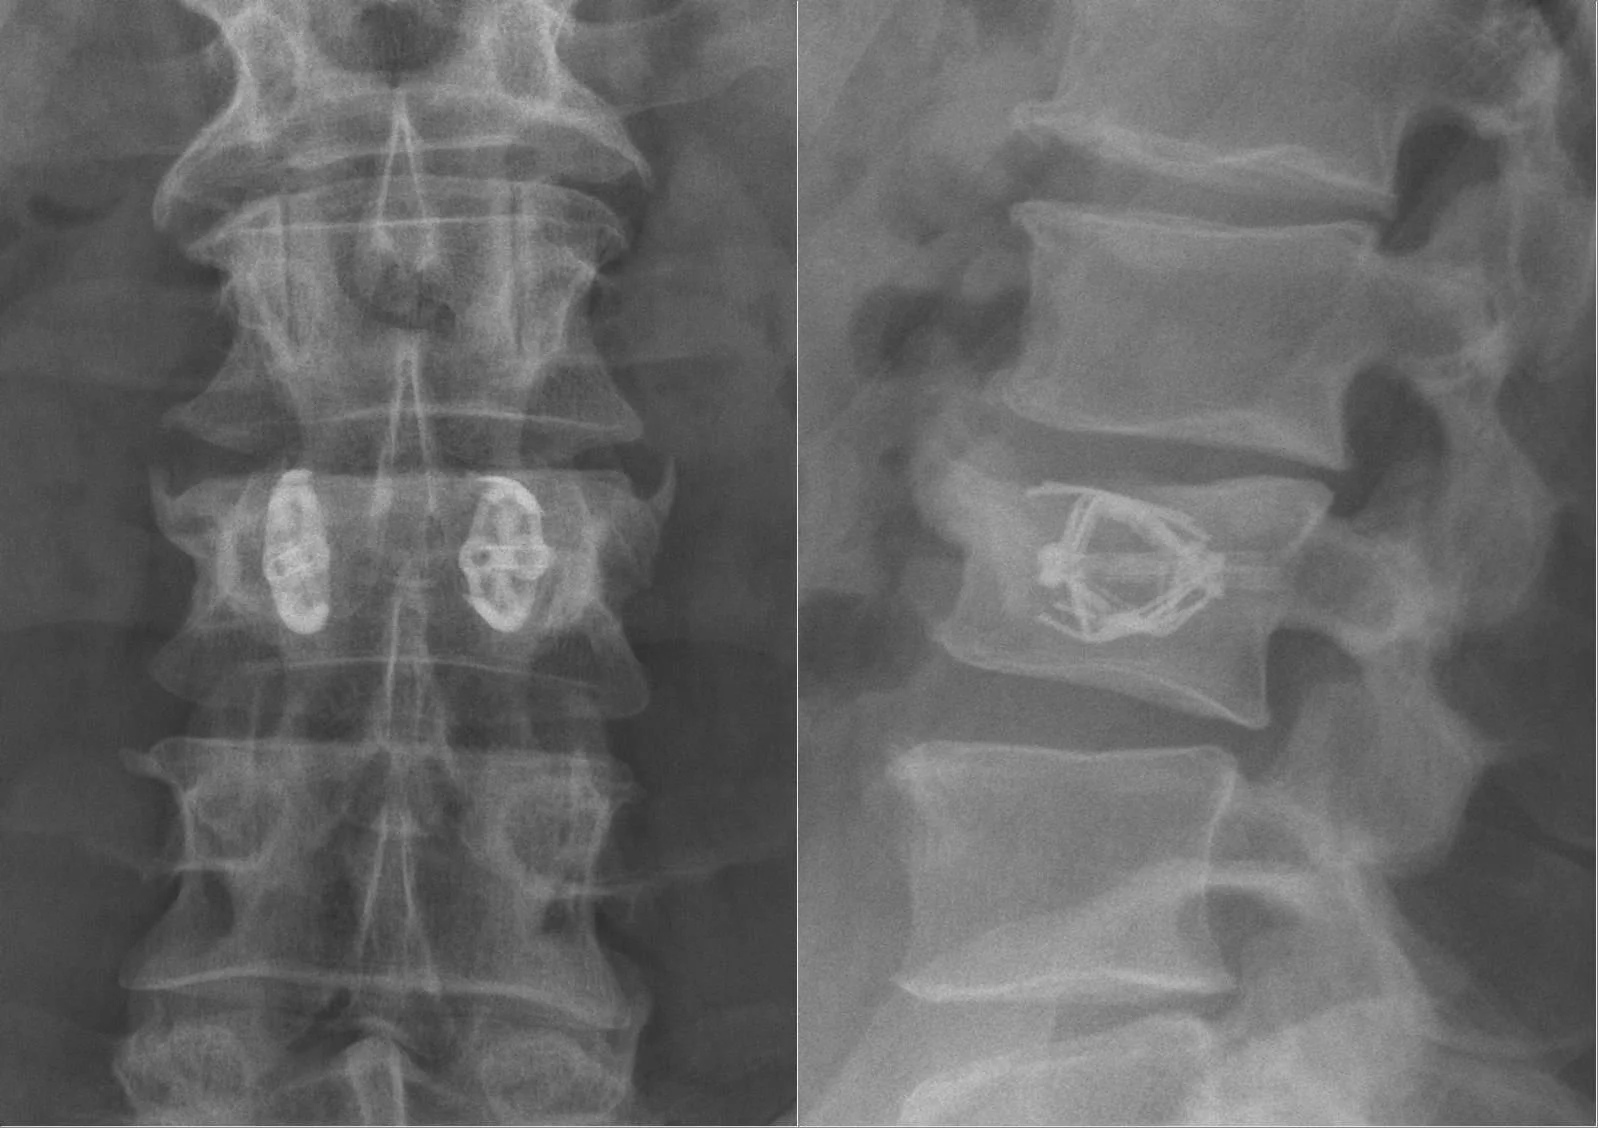

Spinal Fracture Treatments Vertebral Augmentation Learn More Learn More Spine Jack Procedure Learn More Learn More Get Started With Indiana Vascular, Today! Make An Appointment Make An Appointment Download our Referral Form Download our Referral Form